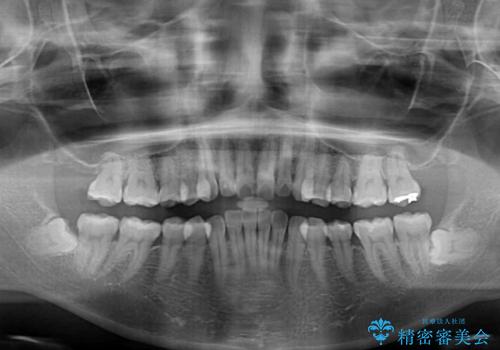

- デコボコと飛び出している前歯を気にして来院された患者様です。

歯列としてはインビザラインでもワイヤー矯正でも対応できるものでしたが、奥歯の咬み合わせを見た時に上顎がやや前方にあり、インビザライン単独では時間のかかってしまう可能性があるため、補助装置を治療当初に使用することで、インビザラインによる治療をスムーズに行えるように計画しました。